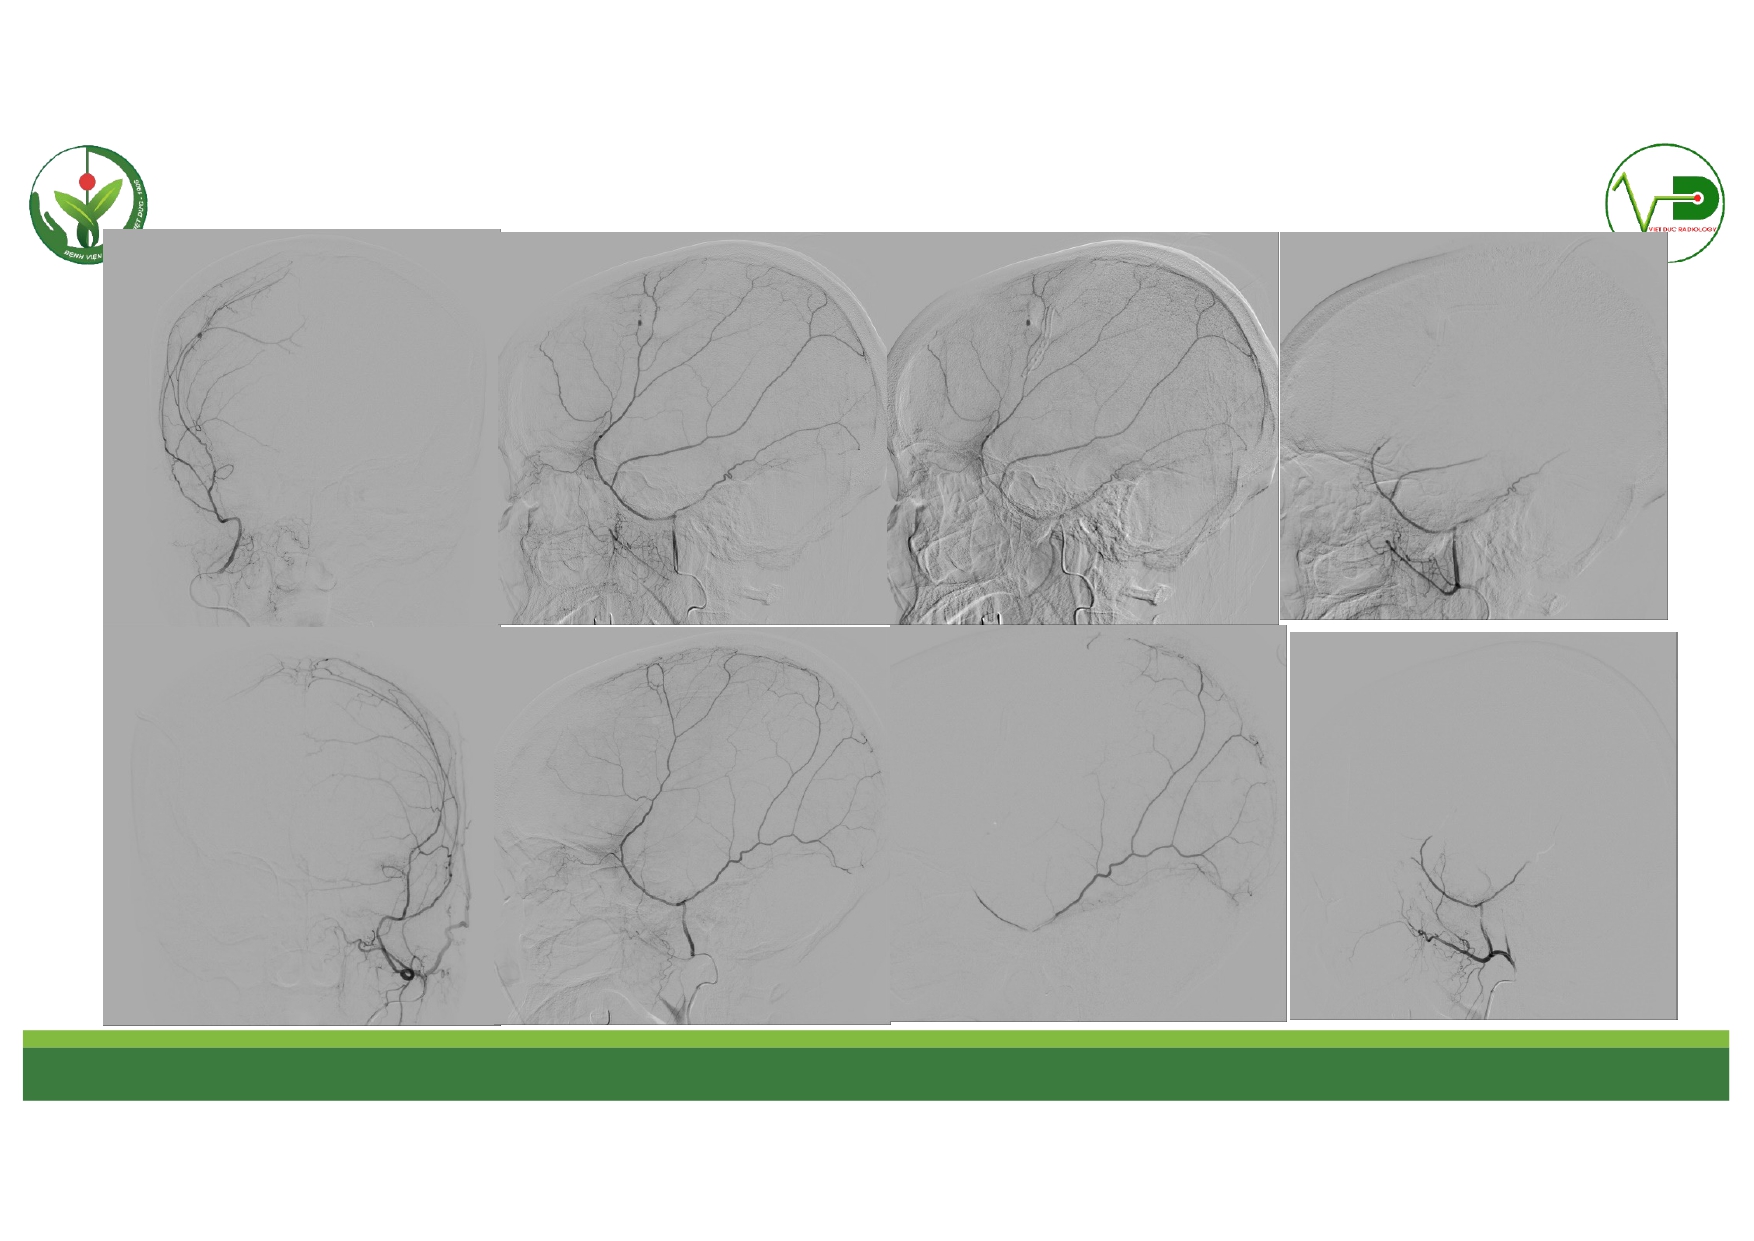

| 13:30 - 14:10 | Surgical management of skull base trauma Endovascular Management of Post-Traumatic Intracranial Vascular Lesions | Assoc. Prof. Nguyen Trong Yen Dr. Nguyen Ngoc Cuong | |

| 15:10 - 16:10 | Interactive Case Demonstration and Discussion II: ~20 minutes each, (5 minutes presentation followed by 15 minutes discussion) Practicals: How I am doing it? Participants present case presentations about how they do it? The faculty comment on and discussion. 1. Endoscopic approach in post-traumatic CSF leakage - Dr. Nguyen Thanh Xuan 2. Endovascular approach in CCF - Assoc. Prof. Le Thanh Dung | Prof. Christian Matula International & local faculties Participants | |